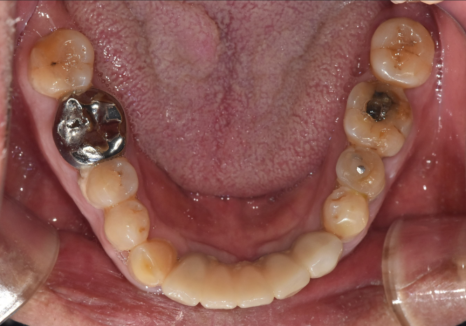

이 환자분은

오랫동안 전체 틀니를 사용해 오셨고,

당뇨 합병증까지 겹쳐

잇몸 상태가 많이 약해진 상태였습니다.

방사선 사진을 보니

잇몸뼈가 전체적으로 아주 얇아져 있었죠.